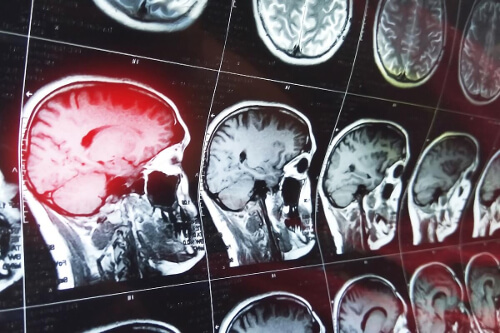

Przyczyny zaburzeń pamięci wywołujących konfabulacje u pacjentów wiążą się z uszkodzeniem czołowej części mózgu. W szczególności dotknięty obszar to przednia powierzchnia podstawna, w której znajdują się obszary oczodołowo-czołowe i brzuszno-przyśrodkowe.